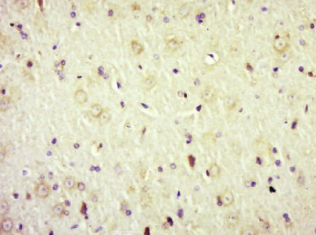

多聚甲醛固定,石蜡包埋(大鼠肝脏);用柠檬酸钠缓冲液(pH6.0)煮沸15min;用3%过氧化氢阻断内源过氧化物酶20分钟;阻断缓冲液(正常山羊血清)37℃ 30min;抗体(AdRB2)多克隆抗体在1:500过夜孵育。在4°C温度下,然后用共轭二次进行20分钟的DAB染色。